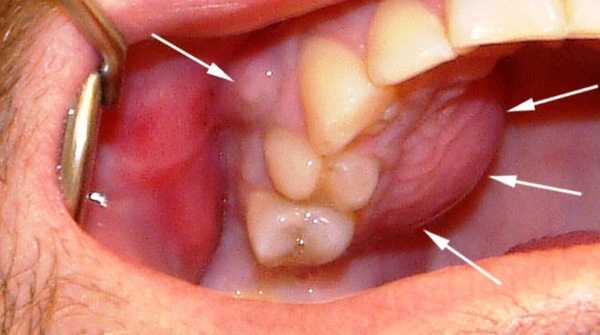

ΠΠ° ΡΠΎΡΠΎ Π²ΠΈΠ΄Π½ΠΎ, ΠΊΠ°ΠΊ Π½Π°Π»ΠΈΡΠΈΠ΅ Π·Π°Π·ΠΎΡΠ° Π² ΠΎΡΡΠΎΠΏΠ΅Π΄ΠΈΡΠ΅ΡΠΊΠΎΠΉ ΠΊΠΎΠ½ΡΡΡΡΠΊΡΠΈΠΈ ΠΌΠΎΠΆΠ΅Ρ ΠΏΡΠΎΠ²ΠΎΡΠΈΡΠΎΠ²Π°ΡΡ ΡΠ°Π·Π²ΠΈΡΠΈΠ΅ Π³Π½ΠΎΠΉΠ½ΠΎΠ³ΠΎ ΠΏΡΠΎΡΠ΅ΡΡΠ° Π΄Π΅ΡΠ½Ρ.

| Π‘ΠΊΠ²ΠΎΠ·Ρ ΠΏΠ°ΡΠΎΠ΄ΠΎΠ½ΡΠ°Π»ΡΠ½ΡΠ΅ ΠΊΠ°ΡΠΌΠ°Π½Ρ | ΠΡΠΈ Π±ΠΎΠ»Π΅Π·Π½ΡΡ ΡΠΊΠ°Π½Π΅ΠΉ ΠΏΠ°ΡΠΎΠ΄ΠΎΠ½ΡΠ° (Π² ΠΎΡΠ½ΠΎΠ²Π½ΠΎΠΌ ΠΏΠ°ΡΠΎΠ΄ΠΎΠ½ΡΠΈΡ, ΠΏΠ°ΡΠΎΠ΄ΠΎΠ½ΡΠΎΠ·) | ![]() ΠΠΎΡΠΏΠ°Π»Π΅Π½ΠΈΠ΅ Π΄Π΅ΡΠ½Ρ Ρ Π½Π°ΡΡΡΠ΅Π½ΠΈΠ΅ΠΌ ΠΊΡΠ°Π΅Π²ΠΎΠ³ΠΎ ΠΏΡΠΈΠ»Π΅Π³Π°Π½ΠΈΡ Π² ΡΠΎΡΠ΅ΡΠ°Π½ΠΈΠΈ Ρ ΠΏΠ»ΠΎΡ ΠΎΠΉ Π³ΠΈΠ³ΠΈΠ΅Π½ΠΎΠΉ ΠΏΠΎΠ»ΠΎΡΡΠΈ ΡΡΠ° ΠΏΡΠΈΠ²ΠΎΠ΄ΠΈΡ ΠΊ Π±ΡΡΡΡΠΎΠΌΡ ΡΠ°ΡΠΏΡΠΎΡΡΡΠ°Π½Π΅Π½ΠΈΡ ΠΈΠ½ΡΠ΅ΠΊΡΠΈΠΈ Π²Π΄ΠΎΠ»Ρ ΠΊΠΎΡΠ½Ρ Π·ΡΠ±Π°. |